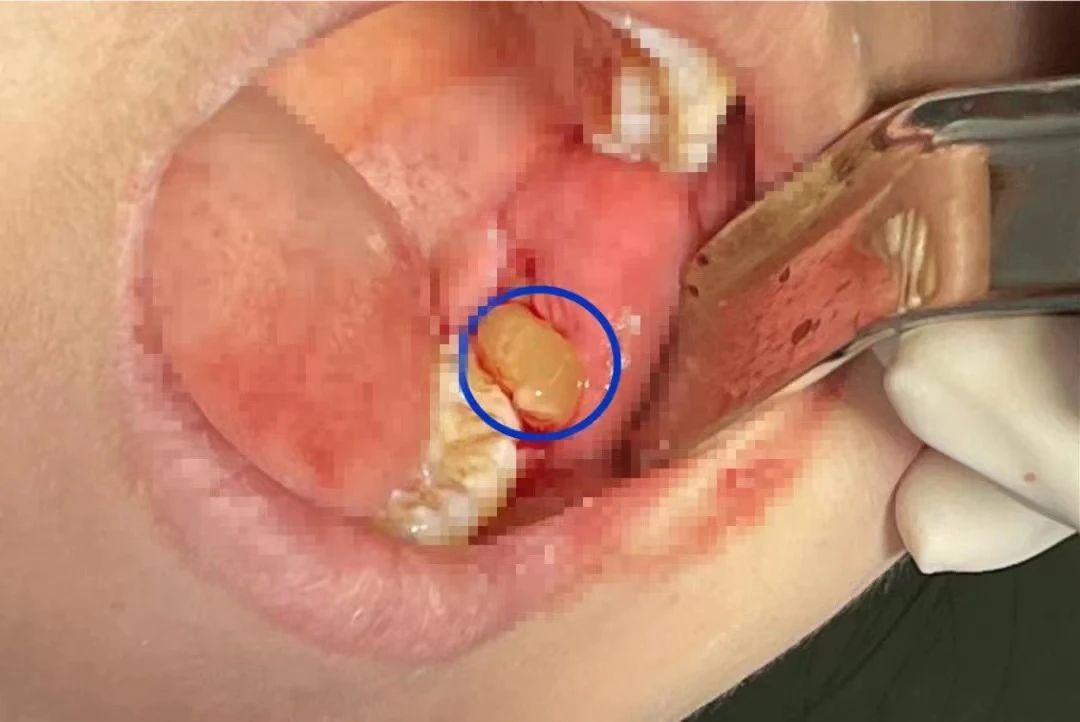

4、放入牙槽窩中。